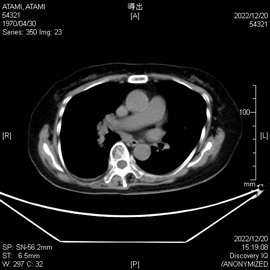

通常のCT画像